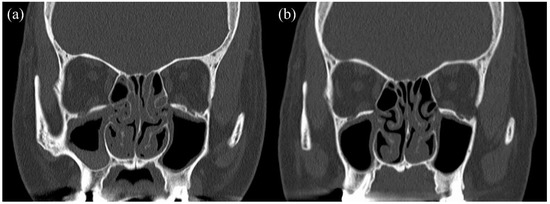

Herein, we describe the case of a 41-year-old woman who was referred for treatment of severe asthma. She was a non-smoker. She had been receiving one puff of vilanterol trifenatate 25 μg and fluticasone furoate 200 μg once daily and two puffs of tiotropium bromide hydrate 2.5 μg once daily. She was also taking montelukast sodium (10 mg daily). As stage lighting staff, she had to miss work once a month due to asthma exacerbation, and she used oral corticosteroids (OCS) for each asthma exacerbation. She reported the loss of her sense of smell, dizziness, and otorrhea, as well as complicated ECRS and EOM. Her EOM was diagnosed when she was 33 years old. She underwent multiple bilateral myringotomy and tympanostomy tubes due to severe EOM. The clinical findings at the first visit were as follows: % predicted FEV1, 37.7%; FeNO, 26 ppb; blood eosinophil count, 2441 cells/μL; total IgE level, 657 IU/mL. Her specific IgE levels for vernal grass, dactylis, Japanese cedar, cypress, and Aspergillus were positive. The ACQ score at that time was 4.4 points. The patient’s treatment course is shown in Figure 1. First, mepolizumab, which is a monoclonal anti-IL-5 antibody, was initiated for severe eosinophil asthma. Three months later, she was no longer absent and her ACQ improved to 2.8 points, but the need for OCS due to frequent exacerbations remained. Thus, we considered that mepolizumab had insufficient therapeutic efficacy and started with omalizumab, an anti-IgE antibody. Two months later, the asthma exacerbation decreased, OCS was no longer necessary, and the % predicted FEV1 improved to 85.2%. However, the loss of her sense of smell, dizziness, and otorrhea caused by ECRS and EOM persisted, and she still had trouble working. Thereafter, these symptoms did not improve, and the blood eosinophil count increased. Nineteen months after the initiation of omalizumab, we switched to benralizumab, which is an anti-IL-5 receptor alpha antibody. During the third month after the initiation of benralizumab, her blood eosinophil counts decreased to 0 cells/μL, and her ACQ improved to 0.2 points. Although we continued treatment with benralizumab for approximately 25 months, her otorrhea, dizziness, and loss of sense of smell worsened. Especially for EOM, there was no improvement in her hearing level, and the therapeutic efficacy was poor. We hypothesized that sequential biologic therapy with benralizumab as anti-IL-5 therapy and dupilumab, which inhibits IL-4 and IL-13 signaling, would have a significant effect in this patient based on the following reasons: (i) the inadequate response to treatment with mepolizumab and omalizumab, (ii) the effects of treatment of asthma with benralizumab, (iii) prolonged high FeNO levels, and (iv) promising data on therapeutic response to dupilumab for ECRS. Therefore, we initiated sequential biotherapy, which comprised a cycle of dupilumab administration four times every 2 weeks for 2 months after a single administration of benralizumab per month for 2 months. Sequential biotherapy was initiated not only to maintain asthma control but also to improve the sense of smell and otorrhea and suppress the progression of ECRS and EOM. Subsequently, asthma control remained well maintained, and the sense of smell, dizziness, hearing level, and otorrhea improved. Moreover, she no longer had any problems with work. Figure 2 shows a sinus CT before and after sequential biotherapy. After sequential biotherapy for 7 months, improvements in sinus shadowing were observed. The ACQ at that time was 0 points, and % predicted FEV1 was 89.9%. She is still undergoing sequential biotherapy.

Figure 2. Sinus CT before and after sequential biotherapy: (a) before sequential biotherapy, (b) after sequential biotherapy for 7 months.